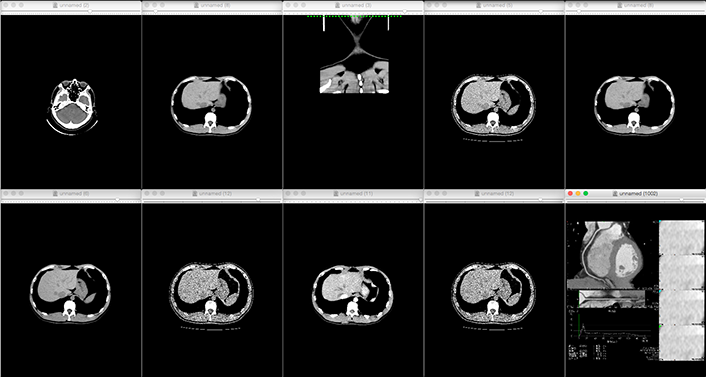

- Reads DICOM data obtained from CT imaging into mimics

- Eliminates noise generated by metal and other materials

-

3D data is converted to images or data to see if the region of interest is

We will confirm with the customer that the area of interest has been reproduced.

The customer will be asked to confirm that the area of interest is reproduced in the image or data.If the STL output is available directly from the medical workstation, the above process is eliminated.

DICOM, which stands for Digital Imaging and COmmunication in Medicine, is the name of a global standard used for the storage and communication of medical images. DICOM was originally developed by the American College of Radiology (ACR) and the North American Electronics Manufacturers Association (NEMA) in 1985, and was renamed DICOM in 1993. In 1993, the name was changed to DICOM, and it came to be used as a standard. In Japan, it was officially recognized as a standard by the former Ministry of Health and Welfare in 1999. JMC can produce high-precision medical models by using DICOM data captured by CT scans and MRIs. Depending on the target area, a model with high reproducibility can be produced if slice images with a pitch of 1 to 2 mm are provided.

3D data extraction from medical CT and MRI data

3D data is essential for the production of models using 3D printers, but it is not always possible to

prepare 3D data in the medical field. In such a case, if you can provide us with DICOM data obtained from

CT or MRI, we can create precise 3D data.

JMC uses a software called "mimics" to construct precise skeletal and organ shapes from DICOM data. JMC

uses mimics software to construct precise shapes of skeletons and organs from DICOM data. By having

specialized engineers perform image processing using mimics, it is possible to extract only the areas of

interest and output higher quality 3D data with less distortion caused by metal products such as gold

teeth and pacemakers.